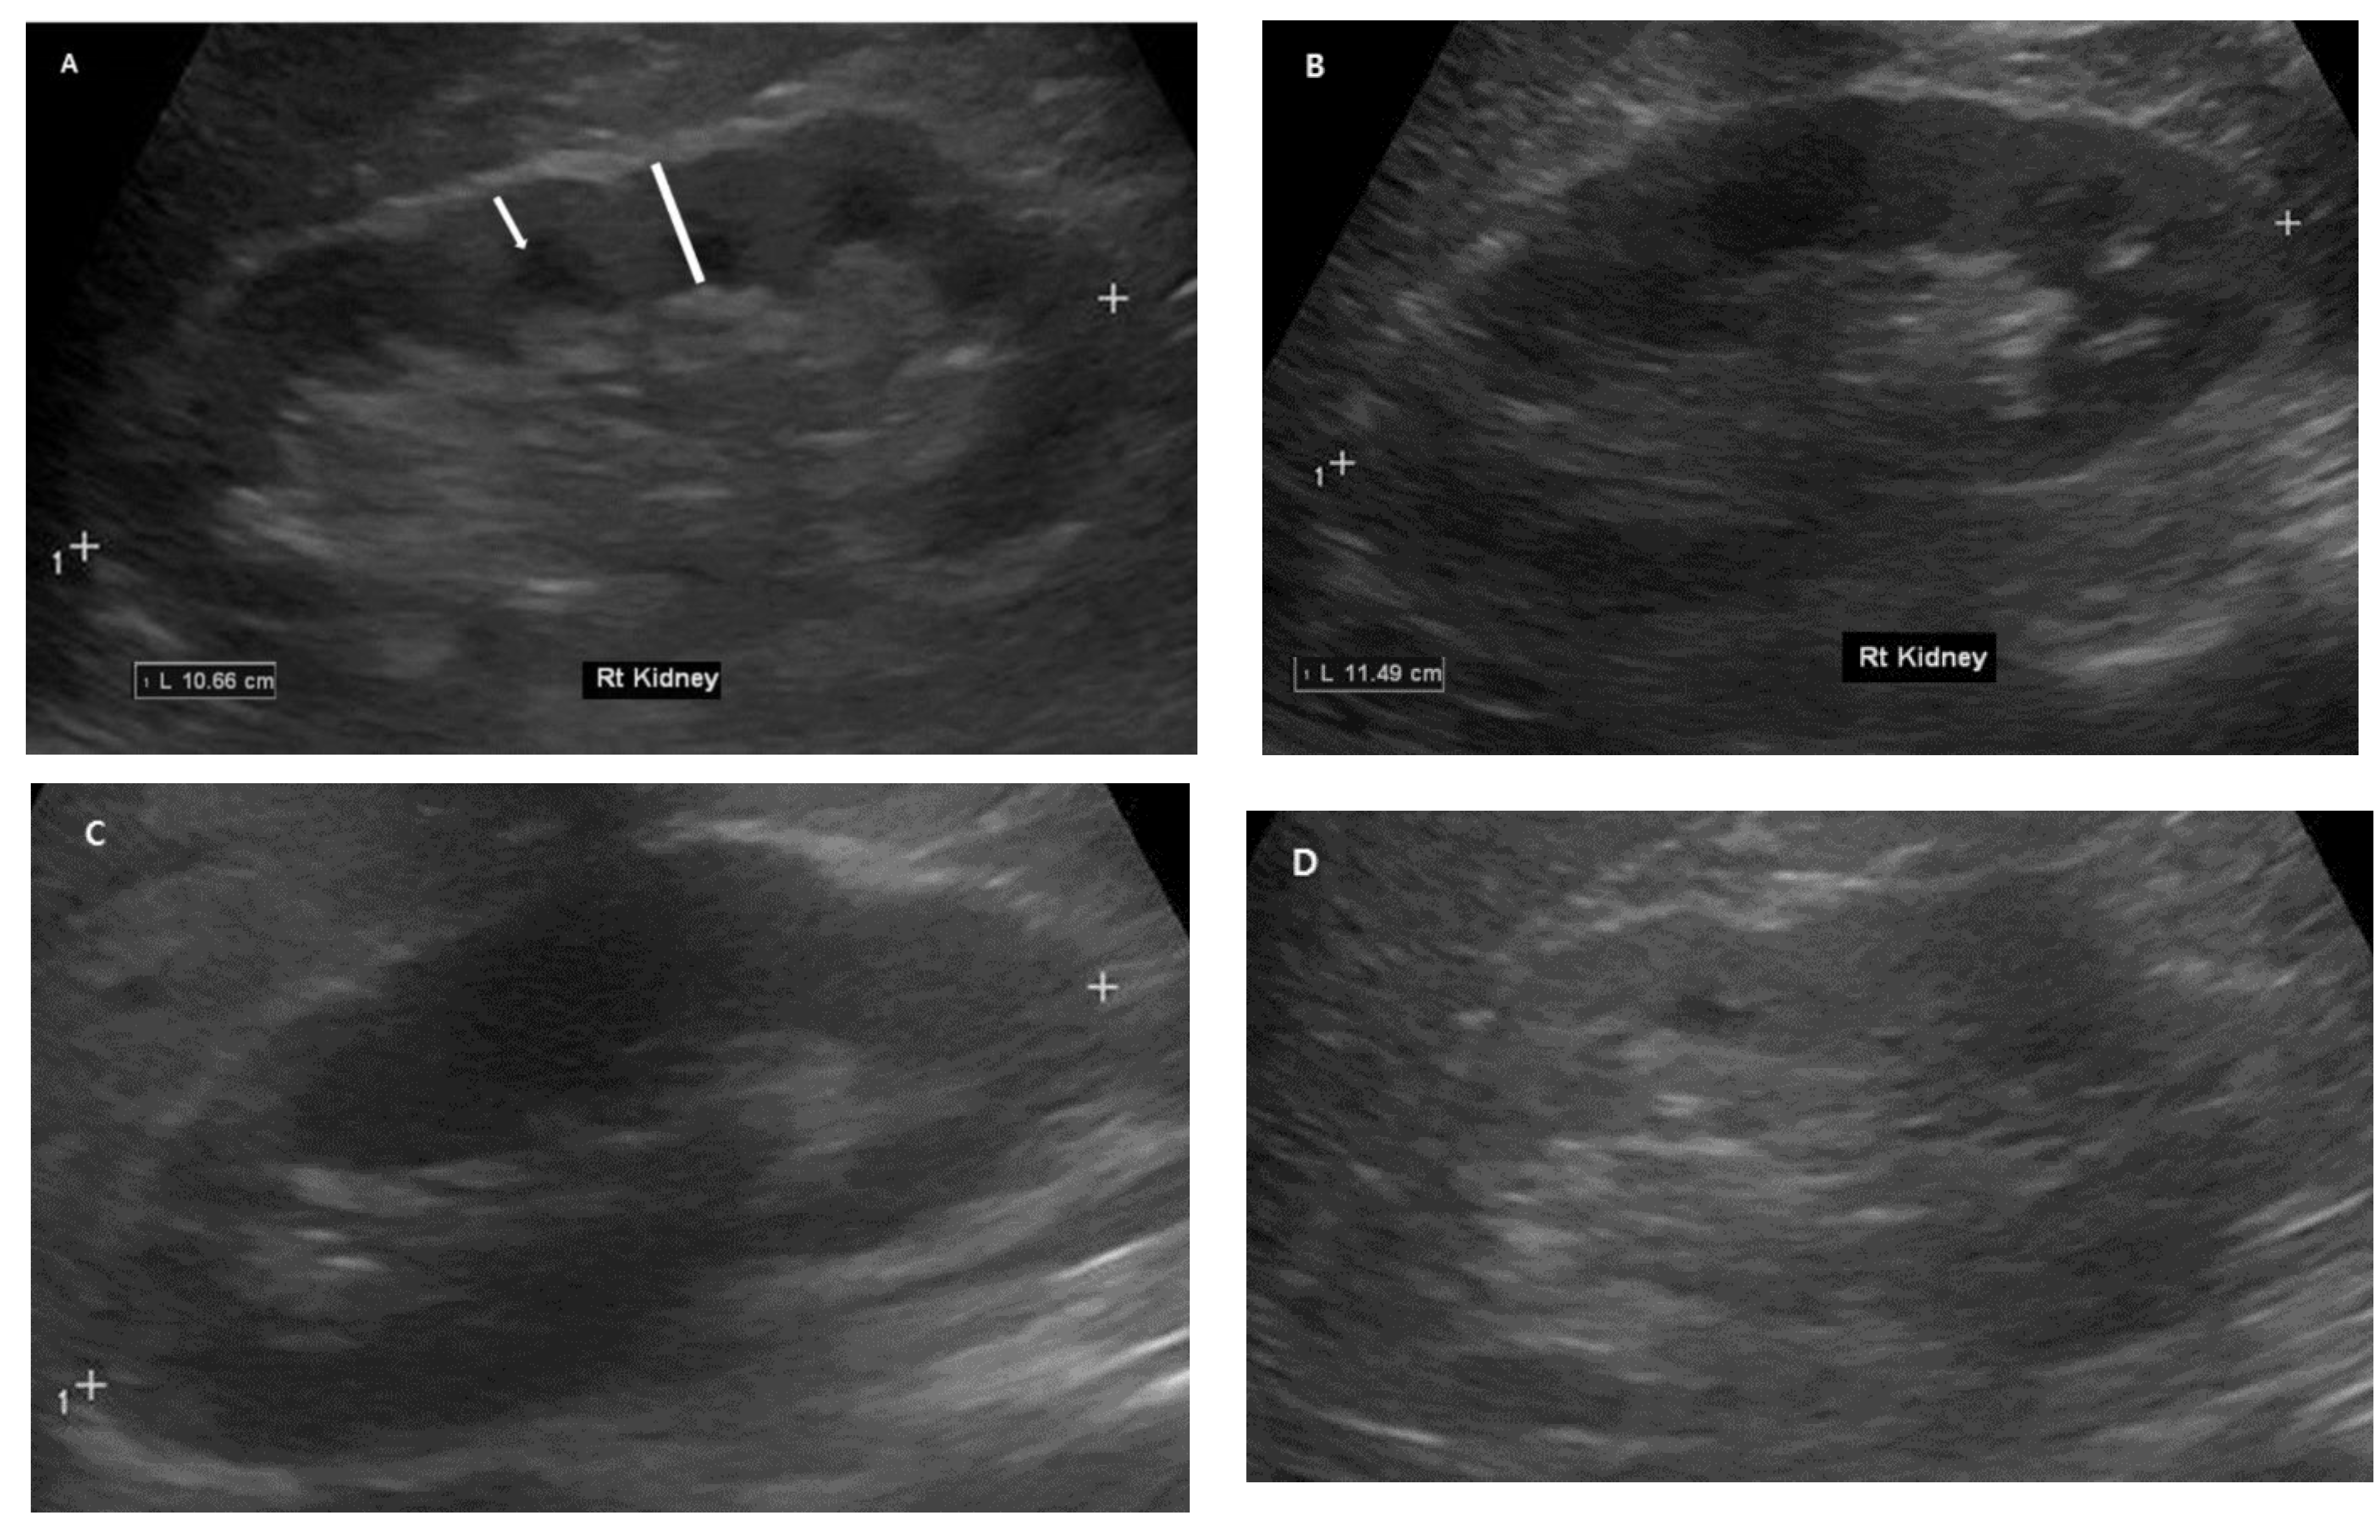

2.4. Renal Ultrasonography Examinations

| RL (cm) | 10.45 ± 0.94 (7.8–13.4) | 10.37 ± 0.95 | 10.55 ± 0.93 | 0.141 |

| CK (cm) | 0.66 ± 0.17 (0.31–1.41) | 0.65 ± 0.16 | 0.69 ± 0.19 | 0.049 |

| PK (cm) | 1.42 ± 0.24 (0.84–2.45) | 1.38 ± 0.23 | 1.49 ± 0.27 | 0.001 |

| CK/PK | 0.46 ± 0.65 (0.29–0.70) | 0.47 ± 0.06 | 0.46 ± 0.07 | 0.447 |

| CK/RK | 0.06 ± 0.01 (0.04–0.12) | 0.06 ± 0.01 | 0.06 ± 0.02 | 0.074 |

| PK/RK | 0.14 ± 0.02 (0.08–0.21) | 0.13 ± 0.02 | 0.14 ± 0.02 | 0.005 |

| RH | 6.44 ± 0.53 (5.28–8.99) | 6.41 ± 0.54 | 6.48 ± 0.51 | 0.150 |

| CKH | 1.03 ± 0.26 (0.52–2.11) | 1.38 ± 0.23 | 1.06 ± 0.28 | 0.147 |

| PKH | 2.22 ± 0.37 (1.45–3.47) | 2.16 ± 0.36 | 2.29 ± 0.37 | 0.007 |

| Irregularity (%) | 0 (71.0%), 1 (22.6%) 3 (6.3%) | 0 (75.8%), 1 (17.4%) 3 (6.7%) | 0 (64.1%), 1 (30.1%) 3 (6.5%) | |

| Echogenicity (%) | 0 (59.1%), 1 (29.8%) 3 (11.1%) | 0 (57.7%), 1 (32.2%) 3 (10.1%) | 0 (61.2%), 1 (26.2%) 3 (12.6%) |